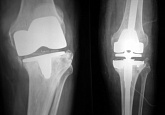

Еndoprosthesis of knee joint

In the late stages of arthrosis of the knee joint, accompanied by a pronounced restriction of the volume of movements, constant intense pain, deformity of the limb, the only way to recover is to replace the affected joint with an artificial joint - arthroplasty.

This method allows you to return the correct form of the limb, the full volume of movements in the joint, relieve the constant pain and crunch during movements and, as a result, significantly improve the patient's quality of life.

Below are presented X-ray photographs and photographs, illustrating the amount of motion in the affected joint before and after surgery.